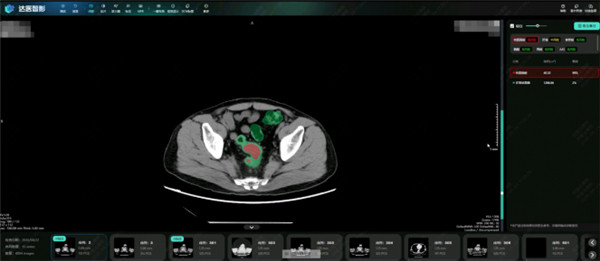

最近阿里达摩院发布的肠癌筛查AI模型DAMO COCA,堪称癌症早筛领域的里程碑。

这是全球首次,证明普通平扫CT就能用于肠癌大规模筛查,彻底告别了传统肠镜筛查的繁琐与不适。

研究团队用超2.7万人的临床数据反复验证,这个AI模型精准找出了5例被漏诊的肠癌患者,敏感性86.6%、特异性高达99.8%,相关成果直接发表在全球肿瘤学顶刊《肿瘤学年鉴》。

不用额外做复杂检查,不用忍受痛苦,花更少的钱,就能精准排查肠癌,这才是真正适合普通人的普惠型早筛技术。